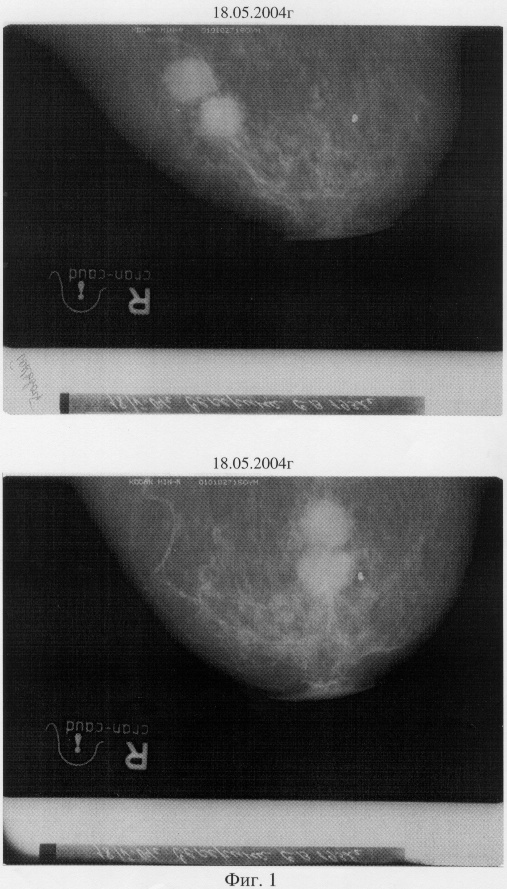

Пример 4. Сенерина С.В., 1931 года рождения. Диагноз: Tumor правой молочной железы (два узла) 5.05.2004 (снимок прилагается – фиг.1), диагноз поставлен рентгенологически, подвержен на УЗИ. От назначенной химиотерапии и лучевой терапии отказалась, принимала тамоксифен. Прошла 105-дневный курс предложенной фитотерапии. На контрольных рентгеновских снимках (фиг.2) от 21.10.2004 наблюдается уменьшение опухолевых узлов в 1,5-2 раза. Субъективные ощущения пациентки позволяют говорить о положительной динамики состояния (на фиг.1 – снимки до лечения, на фиг.2 – после лечения – в 2 ракурсах).